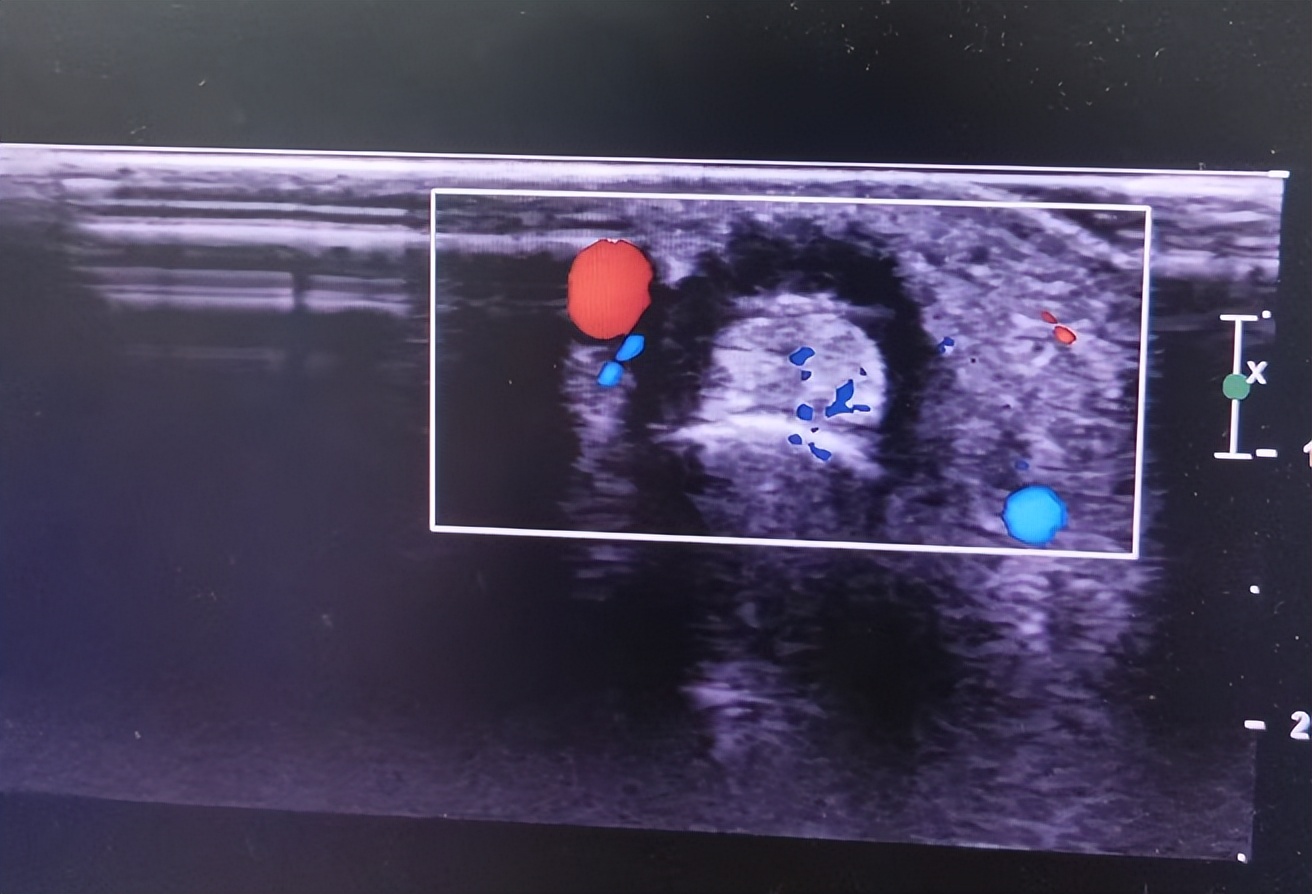

5. 血供评估:通过评估病变区域的血供情况,判断疾病严重程度,并评估临床治疗效果。

肌骨超声能准确显示这些组织的解剖位置、毗邻关系、轮廓、形态、结构、血流分布以及运动状态等,并能对发生于这些组织器官的解剖变异、炎症、退行性变、创伤以及肿瘤等病变进行准确评价。

接诊医生详细询问了大姨的病情,并进行了全面的检查。在排除了其他可能的原因后,医生建议大姨进行超声检查。超声科主任毕晓芳利用肌骨超声对大姨的手腕部进行了精准检查,通过超声动态成像技术,清晰观察到: